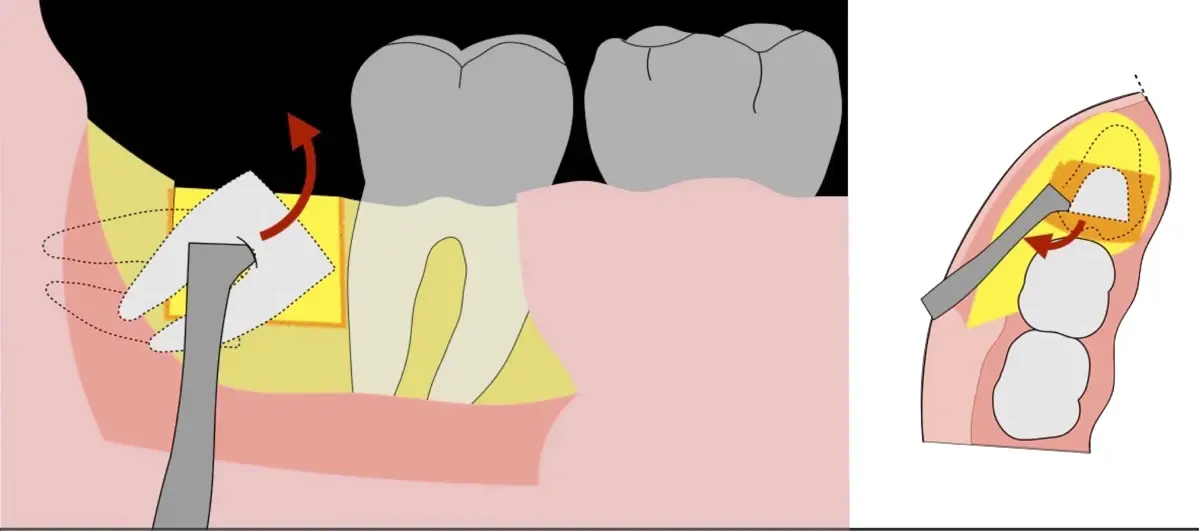

Figura 5. Fractura y eliminación oclusal del fragmento óseo de la porción coronal oclusal.

Figura 6. Demarcación y fractura de la zona de osteotomía a nivel vestibular con inserto aserrado recto y/o angulado.